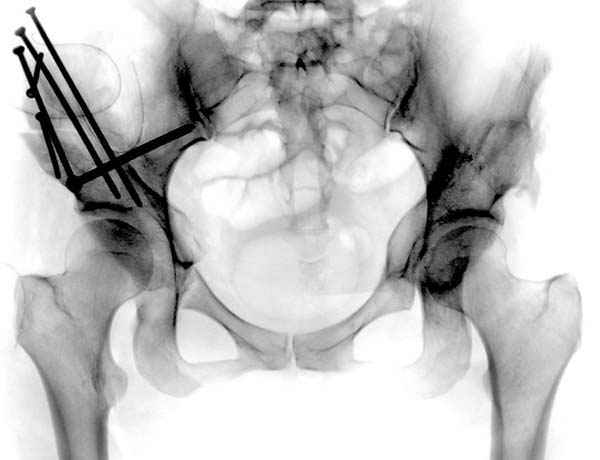

после операции при дисплазии тазобедренного

сустава #4

№ 4-6 после операции при дисплазии тазобедренного

сустава